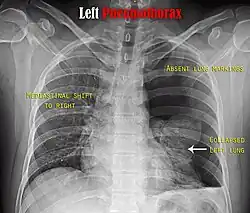

Image from a computed tomography (CT) scan of the chest. On the right (left side of the patient) there is a black area suggesting free air inside the chest

CT scan of the chest showing a pneumothorax on the person's left side (right side on the image). A chest tube is in place (small black mark on the right side of the image), the air-filled pleural cavity (black) and ribs (white) can be seen. The heart can be seen in the center.